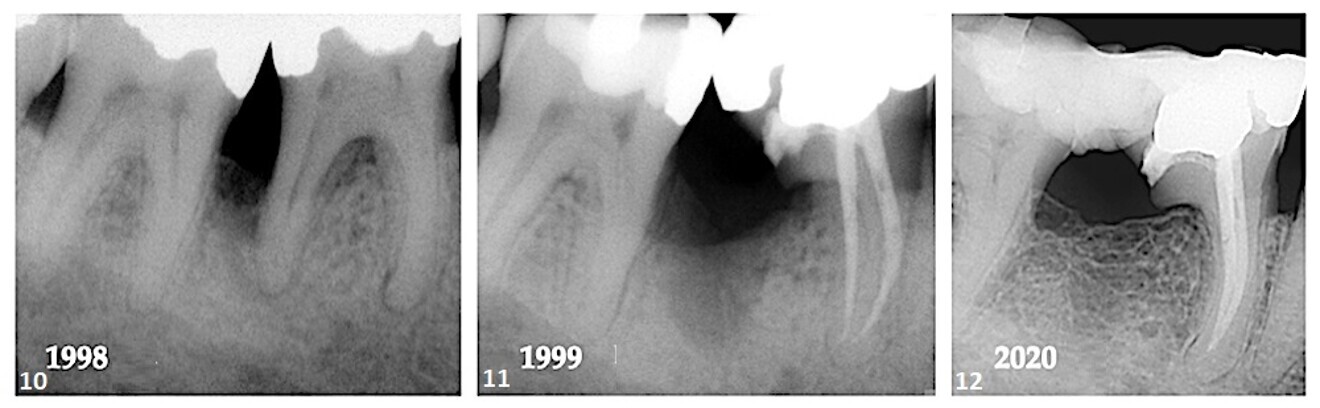

In October 1998, a 39-year-old male patient presented to the office complaining of gingival tenderness in the mandibular right quadrant. Extensive bone loss was noted interproximally between tooth #47 and tooth #46; however, the periodontal status of the dentition in general was within normal limits. Pulp sensibility testing of the teeth in the mandibular right quadrant identified the pulp of tooth #46 to be necrotic (Fig. 10). It was explained to the patient that treatment of periodontal and endodontic lesions was in general unfavourable and that success depended on the severity of bone loss, root trunk length, degree of root separation, curvature of the root to be resected, ability to eradicate the osseous defect, pulpal status, and restorative and oral hygiene procedures required.

With the patient’s consent, the distal root of tooth #46 was resected and the overlying crown portion retained (Fig. 11). At some point after the amputation procedure, the referring dentist splinted teeth #47 and 46 with a composite and Ribbond bridge. Twenty-two years after the initial procedure, osseous regeneration and cortication in the furcal region were evident between teeth #47 and 46 (Fig. 12).

Case 2—Fig. 10: Loss of bone between tooth #47 and tooth #46 and loss of the periodontal ligament around the apical region of the mesial and distal roots were evident. Fig. 11: After resection of the distal root, the degree of bone loss appeared to have increased. Fig. 12: A 22-year follow-up showed regeneration of the lost interproximal bone and cortication of the alveolar crest.